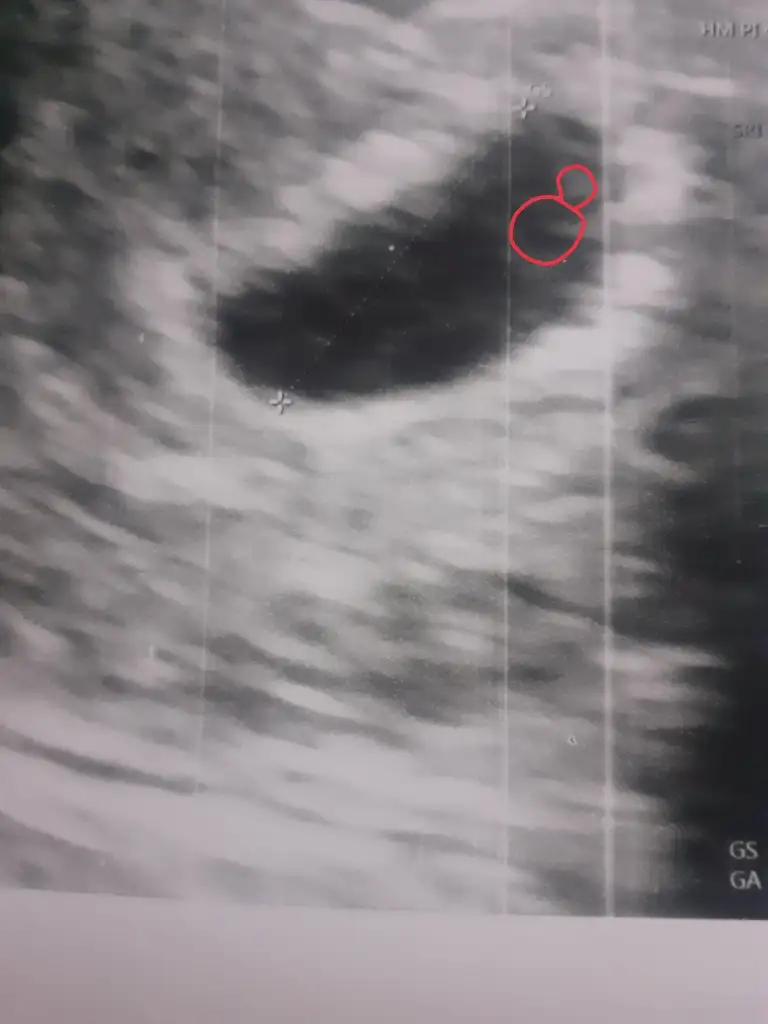

Bende o yüzük gibi şeyden yok o ne demek onu da bilmiyorum kızlar biri bakabilir mi😄

Eklentiler

• 2E2DA8B9-3EA3-4F46-BC43-468814B723A1.webp

2E2DA8B9-3EA3-4F46-BC43-468814B723A1.webp

24,7 KB · Görüntüleme: 70